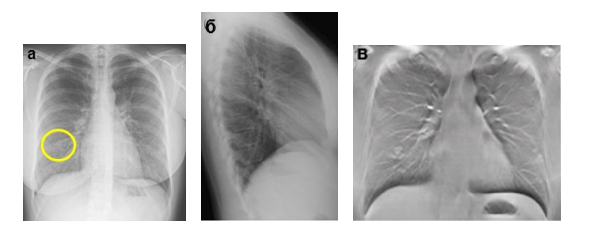

Метастатическое поражение лёгких: а – цифровая рентгенограмма ОГК в прямой проекции; б – цифровая рентгенограмма ОГК в правой боковой проекции; в, г, д, е – ТС ОГК.

Пациентка с диагнозом рак молочной железы. В средней доле правого лёгкого неотчётливо определяется округлой формы очаговая тень средней интенсивности с неровными контурами. На ТС в средней доле правого лёгкого выявляется группа очагов (желтый круг), дополнительно в обоих лёгких определяются множественные очаги неправильной формы, размерами до 10 мм (желтые круги). Заключение: Метастазы в обоих лёгких.